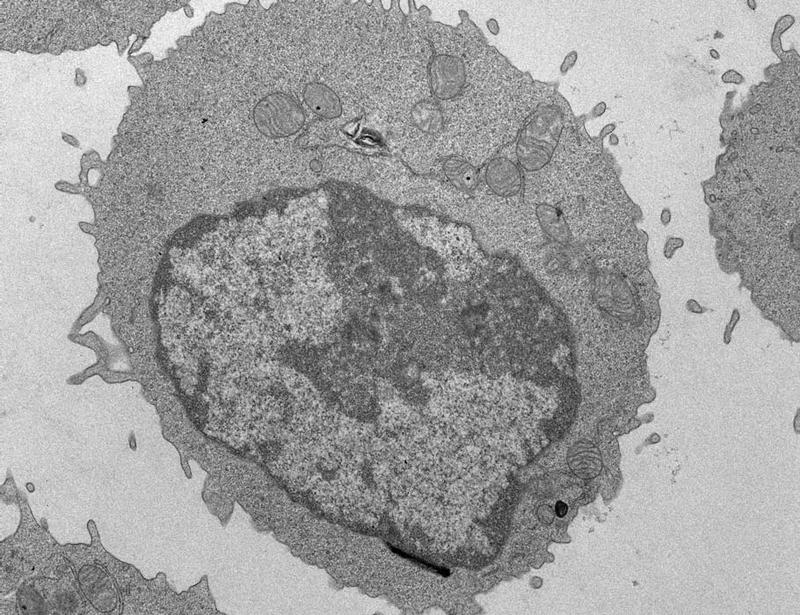

Palmitate impairs CD8 T cell mitochondria, suppresses histone acetylation and chromatin accessibility, and blocks effector programs.

Palmitate-induced mitochondrial damage restricts histone acetylation in CD8 T cells to impair antitumor immunity | Science Immunology